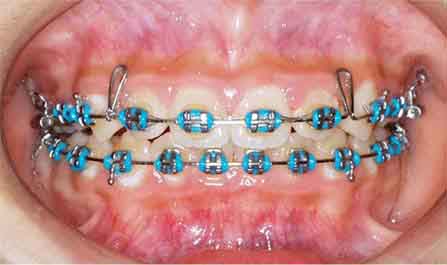

治療開始1年後